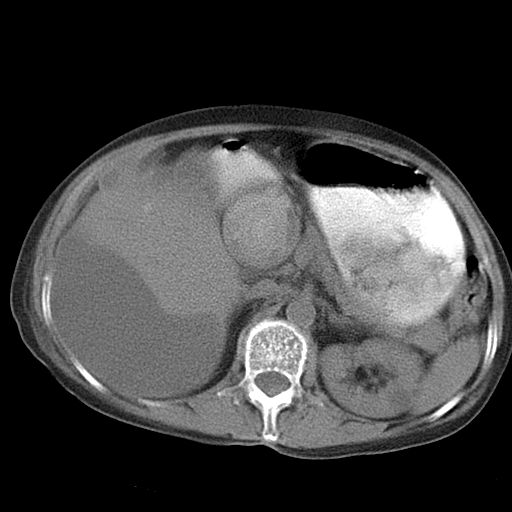

以下是引用dyqct在2006-12-7 21:08:00的发言:[br]考虑:1、肝内外胆管多发性结石伴肝左叶外侧段肝萎缩;[br] 2、右膈下多发脓肿;[br] 3、右侧少量胸腔积液、斜裂积液;[br] 4、左肾囊肿。

以下是引用jiazh在2006-12-7 20:37:00的发言:[br]肝脏周围半狐形低密度影,肝脏表面受压推移,考虑膈下脓肿可能性大;2、右侧胸腔积液

以下是引用拾荒者在2006-12-7 21:44:00的发言:[br]肝内外胆管多发结石,右膈下多发脓肿,右胸膜腔及叶间裂积液,左肾囊肿。[br] [br]